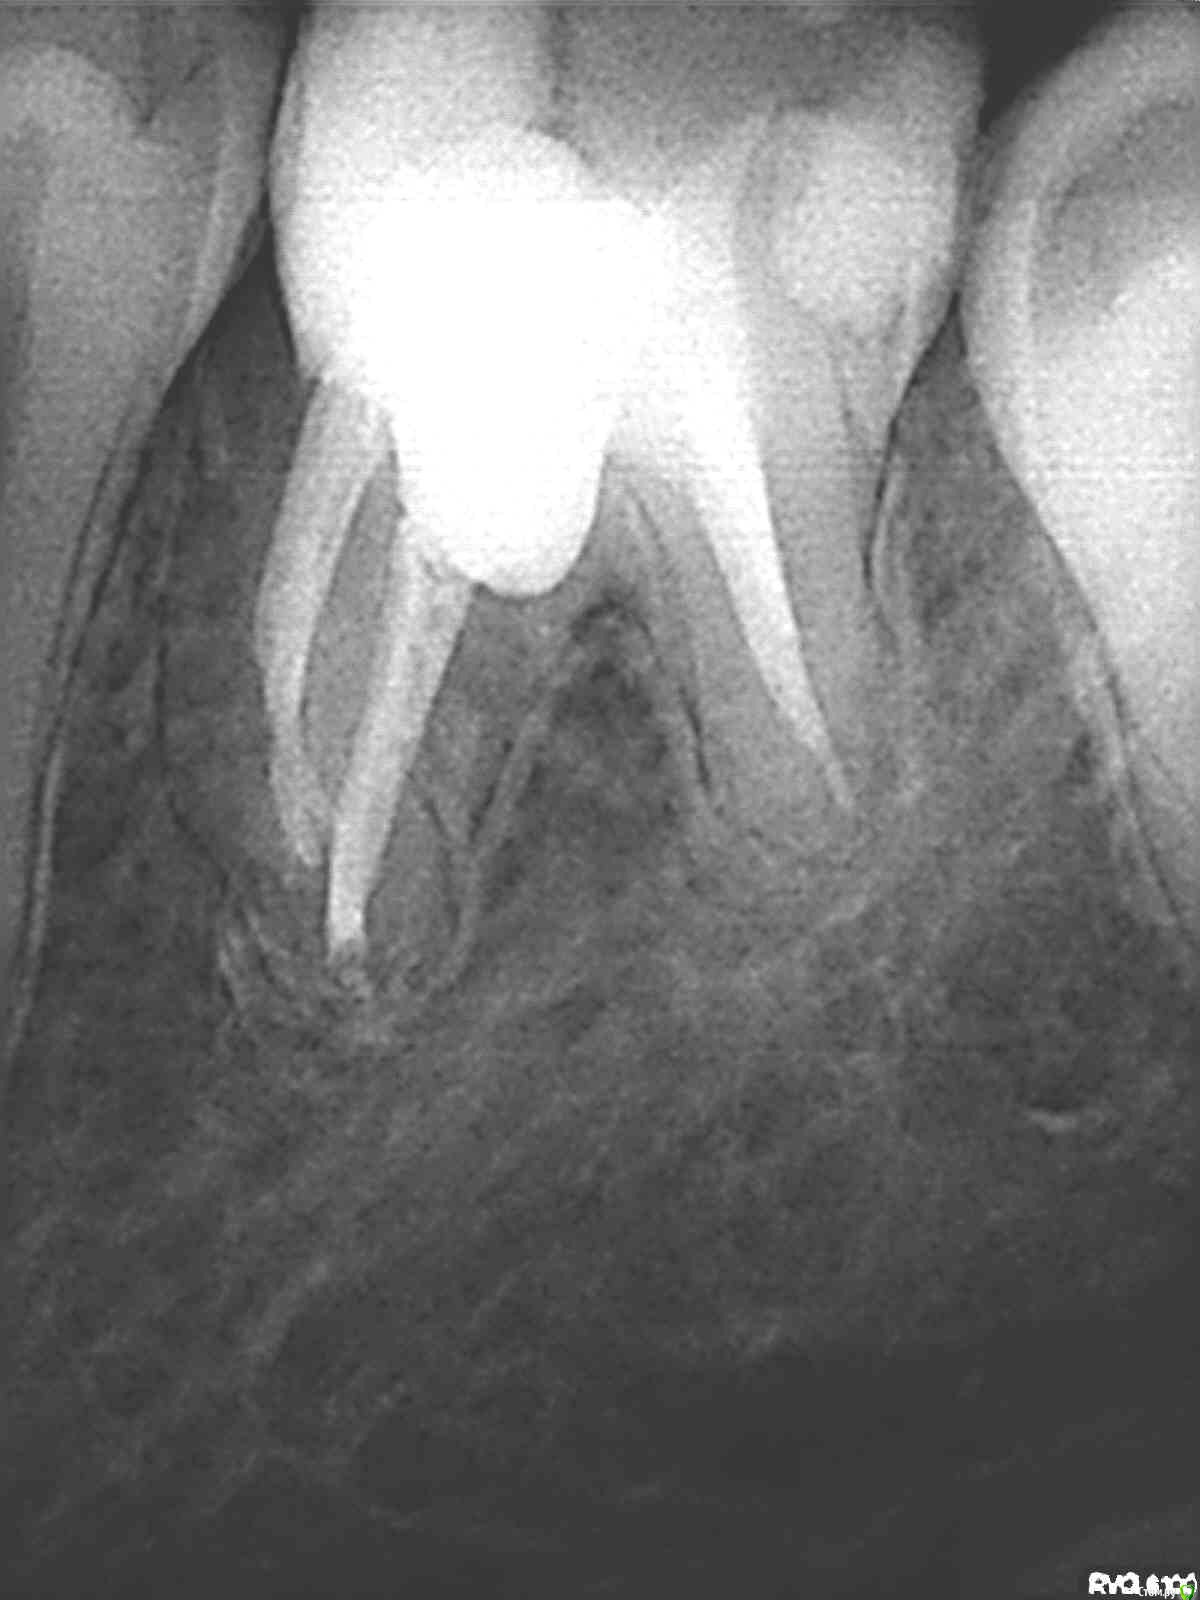

igorstom Опубликовано 10 декабря, 2016 Автор Поделиться Опубликовано 10 декабря, 2016 И вот наконец заставил сделать контрольный снимок. К сожалению далеко не всех можно пронаблюдать пациентов. Хотя есть в планах создать тему "Отдаленные результаты". Есть пациенты, которые наблюдаются более 8 лет.Вопрос. Гранулема исчезла? Или снимок просто не показывает? Раньше зуб периодически при переохлаждении или простуде всегда давал знать. Сейчас более 1,5 лет ни разу не пискнул. Об эндо чуть позже напишу. Ссылка на комментарий